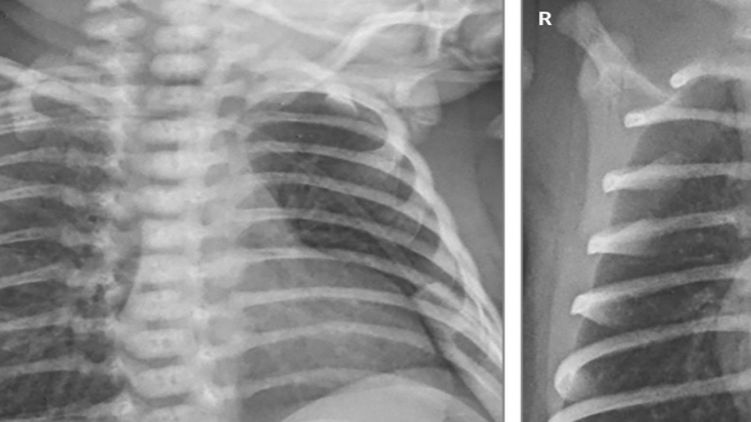

Кроме пневмонии, у двоих маленьких пациентов проявилась лихорадка, а у недоношенного ребенка, который родился после 31 недели беременности, было подозрение на сепсис, который лечили антибиотиками. В отделении интенсивной терапии они провели 2, 4 и 11 дней (больше всего - недоношенный ребенок, ему также понадобилась искусственная вентиляция легких). Все остались живы.